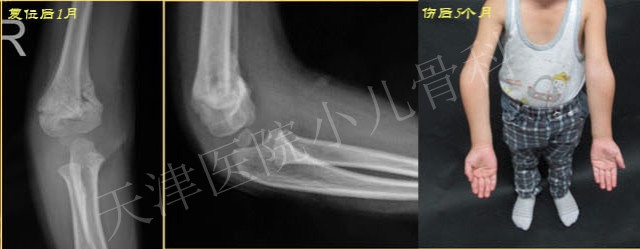

学生:伤后5个月时出现明显的肘内翻畸形。出现肘内翻畸形的可能原因有哪些?

老师:核心有两点:a、这是所谓的“尺侧塌陷型”肱骨髁上骨折,冠状面尺侧塌陷、内侧柱短缩、长度丢失,矢状面前倾角变小。冠状面存在“内翻”倾向,单纯的保守治疗难以重建/维持对位,特别是冠状面的对位;b、石膏托屈肘角度明显不足,不能利用充分屈肘时后方骨膜铰链作用维持复位后的稳定性,骨折端存在旋转不稳定,即使初始获得了良好复位,这样不当的外固定也容易导致复位的丢失。这其实是临床最常见但同时又最容易被忽视的导致肘内翻的髁上骨折类型。